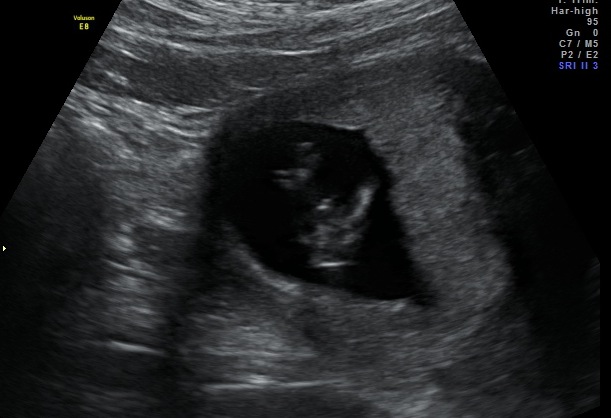

third boy???

Hi, just came back from my nt scan and I'm pretty sure I'm having a third boy.

I've been ttc since 2011 with several mc so either way I'm ok as long as he's healthy, but would like to know your thoughts on my pictures. I don't see any nub on my profile shots so...

It does look boyish. Happy this one is healthy for you!

I think you might be right :) Congrats on your long awaited pregnancy!

Getting boy vibes! Congratulations! I wish you a healthy, uneventful pregnancy!!